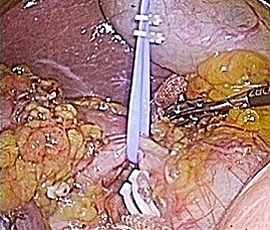

手術画像